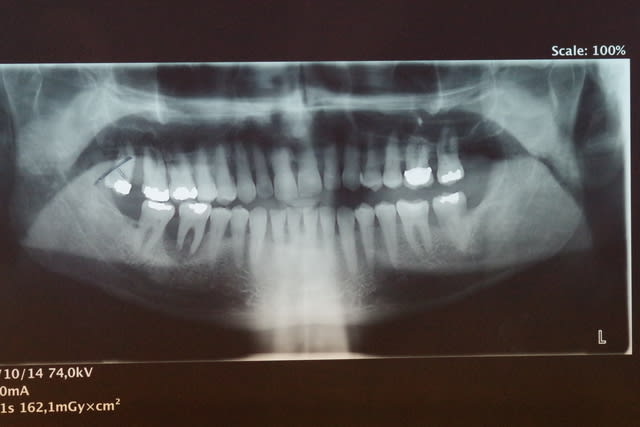

De ce fait la surcharge occlusale sur la 46 a entraîné une lyse osseuse importante qui contre indique la conservation de cette dent.

J'entends par là que ce monsieur a l'ATM gauche luxée, probablement depuis un bout de temps. J'imagine que ça se verrait à la pano si les ATM étaient dans le cadre.

Concernant une radio des ATM, mon centre de radio m'a précisé que cela ne se faisait plus car la SS ne remboursait plus !!

Ils veulent faire une pano centré sur les ATM.

Je pense la faire faire afin d'éliminer définitivement une luxation de la mandibule.

Une pano montrant les ATM permettra de confirmer ou non la théorie de la luxation mandibulaire: plus de doutes possibles. L'IRM permettra d'écarter un autre problème ATM (luxation du disque), qui serait cependant bien étonnante au vu des symptômes.

Je pense aussi qu une pano bouche fermée et une en bouche ouverte serait intéressante pour savoir s il y a une luxation.

> Une pano montrant les ATM

SANS LA CALE INCISIVE : EN OCCLUSION!! ça te permettra de voir la place de tes condyles dans les cavités glénoïdes en occlusion. Si la luxation est permanente tu la verras.

Je vais faire faire au patient ces prochains jours une pano centrée sur les ATM bouche fermée.